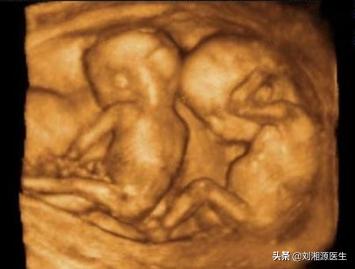

7.患者怀的是双胞胎,必须剖宫产吗?

答:双胎妊娠分娩方式较为复杂,目前没有足够的证据支持双胎妊娠选用哪一种分娩方式更好,建议分娩前与医生充分沟通,结合双胎妊娠的绒毛膜性,第一胎的胎方位,胎儿体重,母体情况,接生者经验和家庭意愿等综合选择。双胎的阴道分娩建议选择二级或三级医院实施,由有丰富经验的产科专家及助产士、新生儿科共同处理。